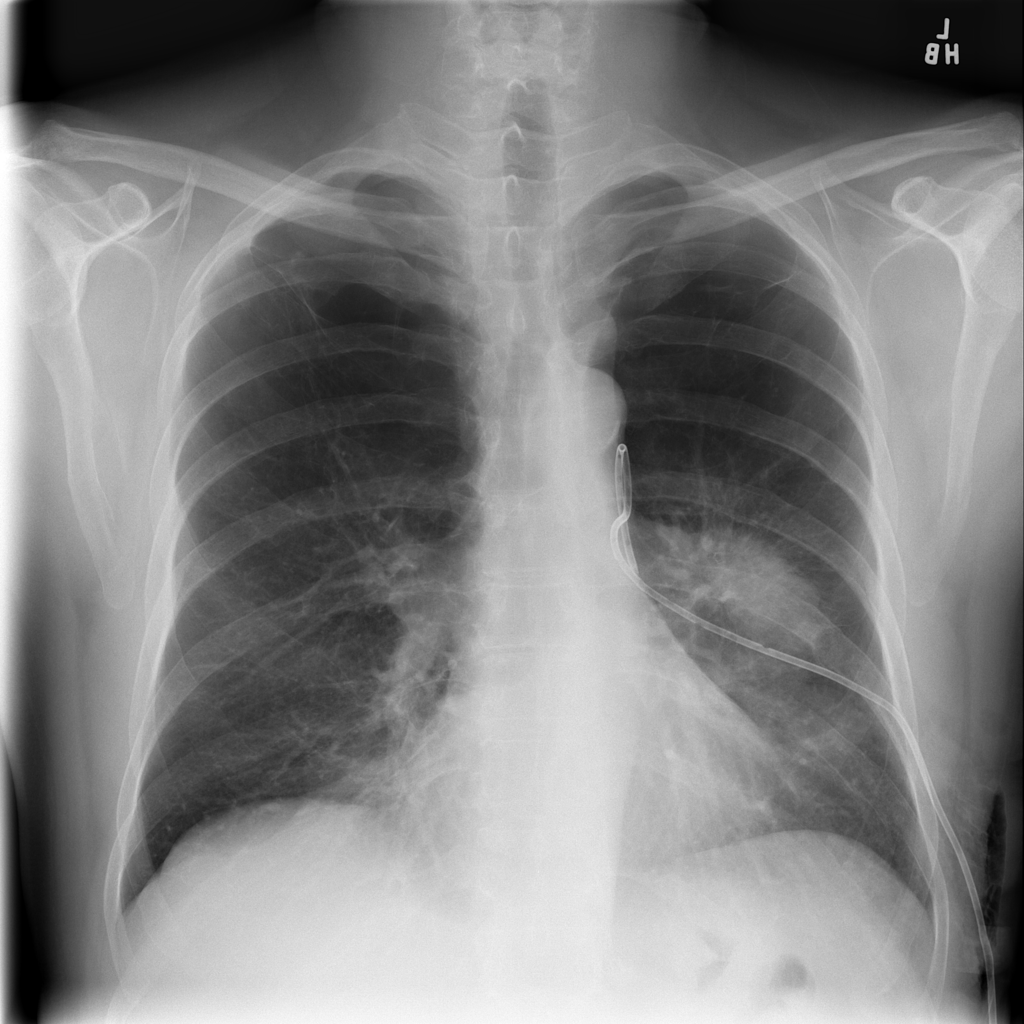

PAT-D7A5 · IMG-000Mass

PAT-D7A5 · IMG-000

PA